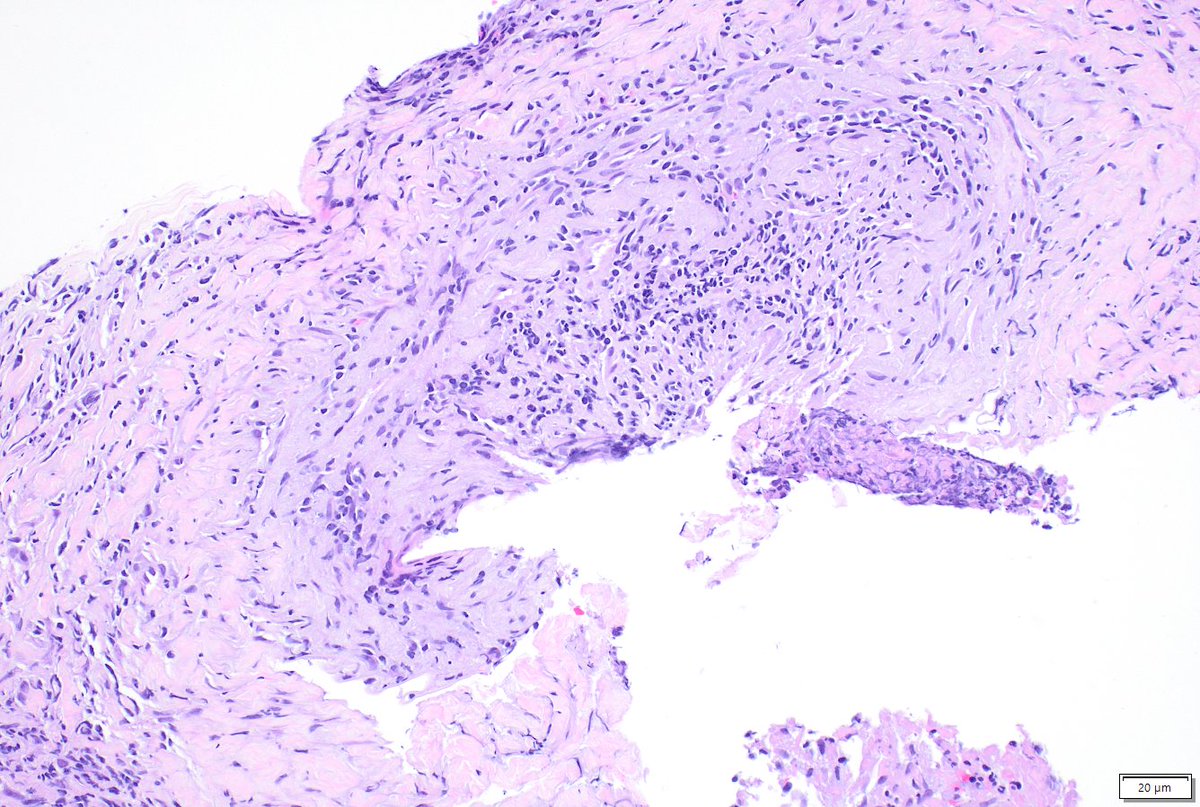

Incidental finding. Resection for met CA + CHF hx. Anything striking in alveolar septae imgs? Consider thoracic path training @MoffittNews "to contribute to the prevention and cure of cancer, focusing on groundbreaking research, expert patient care, and comprehensive education"